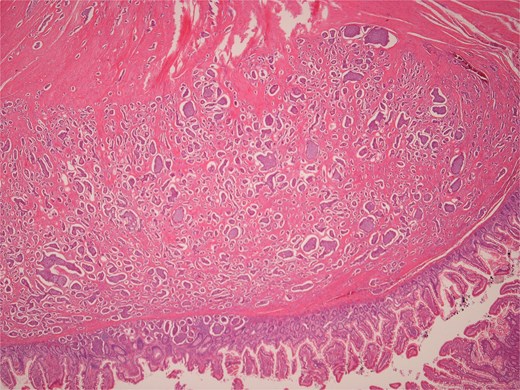

Histopathological examination of surgical specimens revealed three distinct neoplasms: (i) invasive colonic adenocarcinoma (Figs 4 and 5), (ii) jejunal NET (Figs 6 and 7), and (iii) small-lymphocytic lymphoma (Figs 8 and 9). Morphological assessment supported by immunohistochemical profiling confirmed each represented an independent primary, with no evidence of a shared clonal origin. The findings were subsequently reviewed at the Multidisciplinary Meeting alongside Oncology and Haematology specialists, and adjuvant single-agent chemotherapy was initiated, with planned surveillance of the indolent lymphoma.

High power view showing a proliferation of monotonous small lymphoid cells.